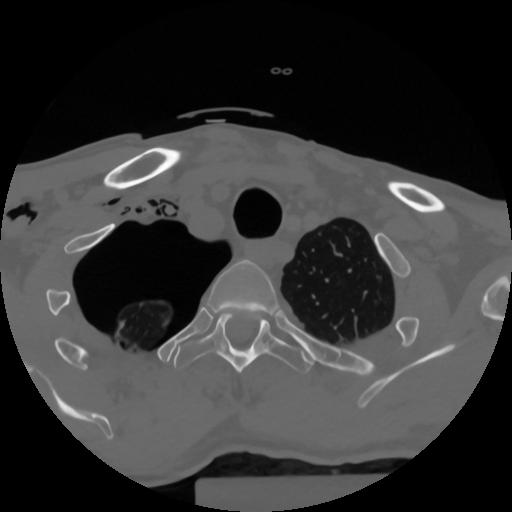

12 P.BLANDAS,,Vol,0.5,P.BLANDAS,,